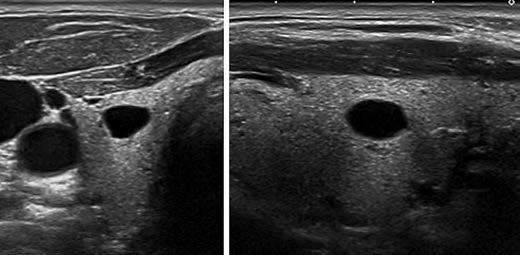

KTIRADS